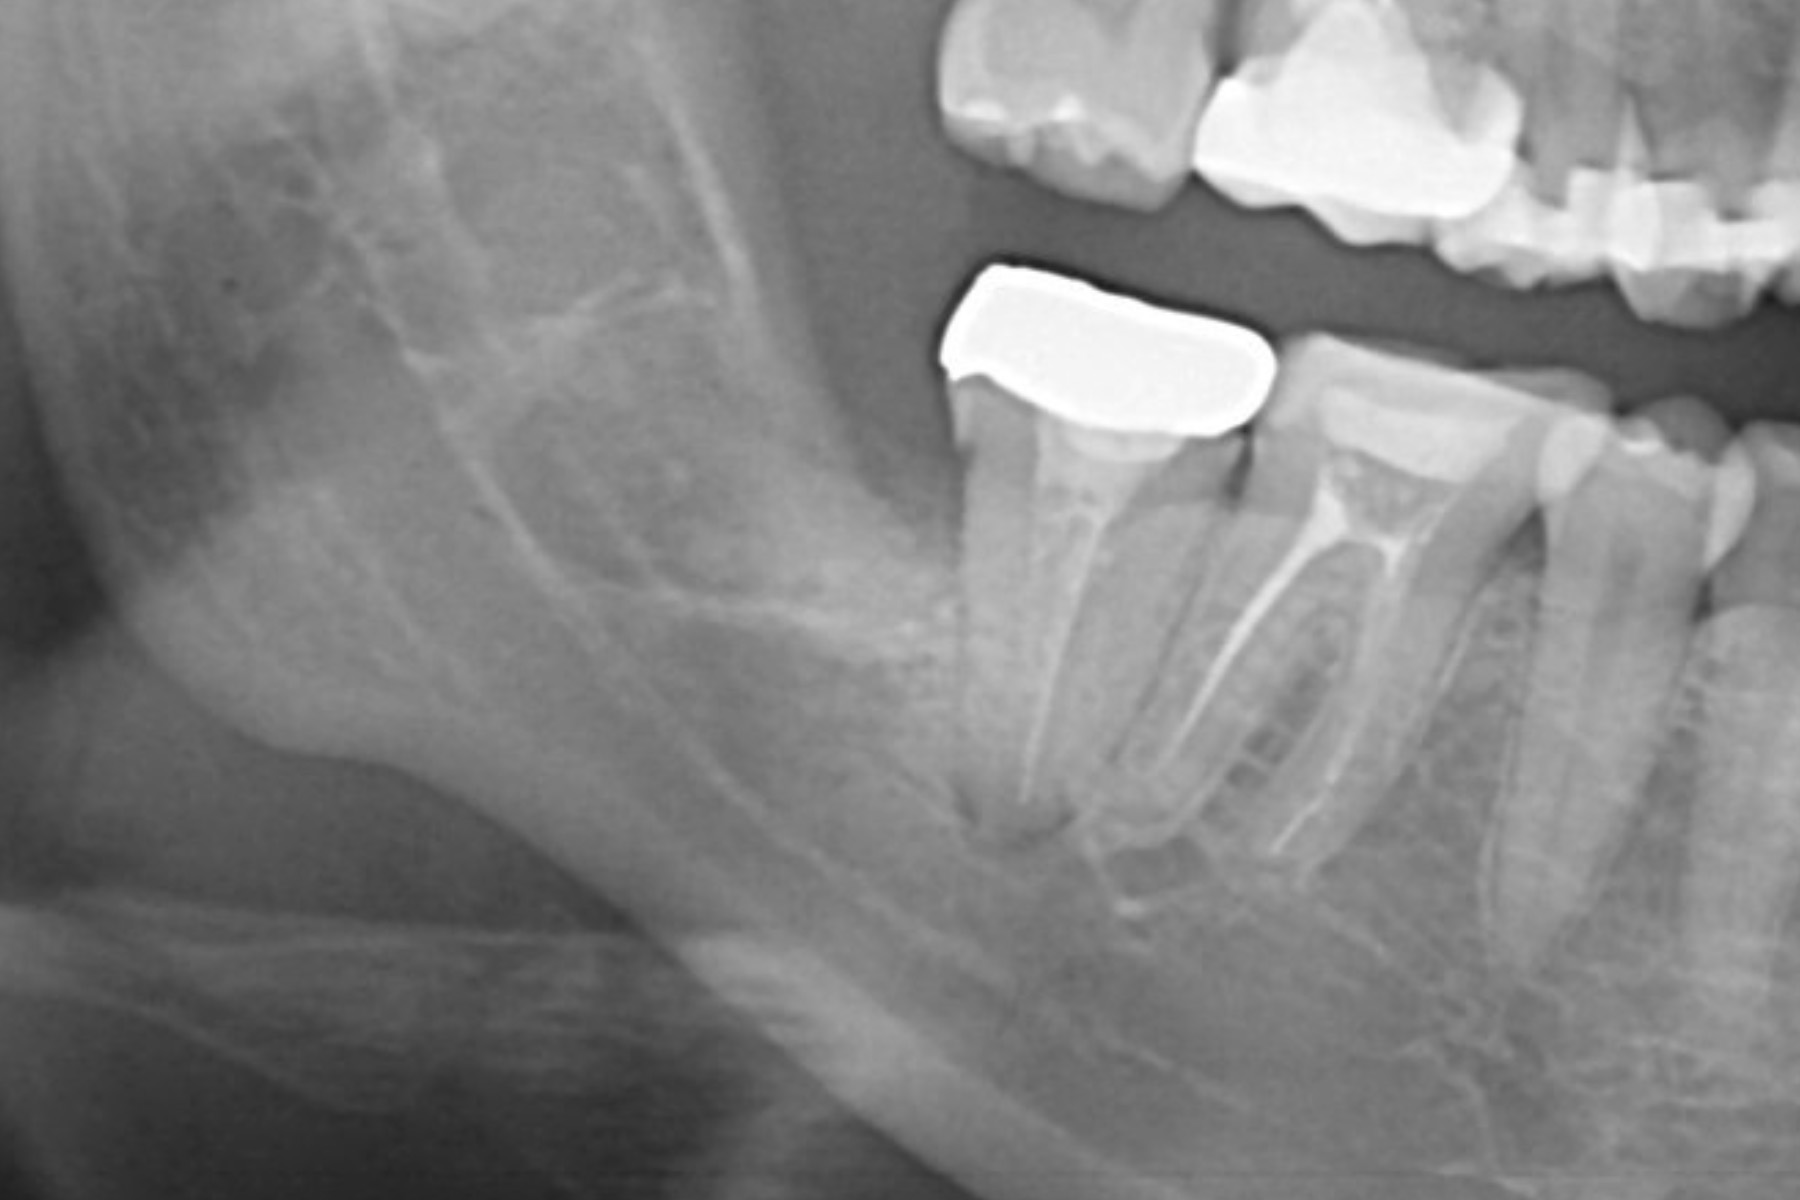

| 主訴 | 奥歯が腫れて膿んでいる |

|---|---|

| 治療内容 | 当該部歯牙は破折しており保存困難であった。抜歯と同時にインプラント埋入手術及び骨造成手術を全て同日に実施することにより手術回数を1度に抑え患者の負担を減らし、かつ通常6〜7ヶ月の治療期間を短縮した。 |

| 治療期間 | 3〜4ヶ月 |

| 治療費 | 約¥600,000〜¥700,000 |

| 治療リスク | 術後疼痛、腫脹。周囲組織の状態によっては追加の処置を要することもある。 |